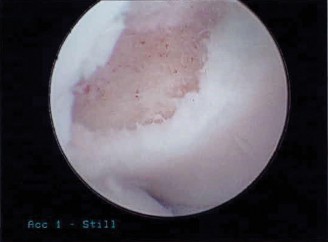

Posterior access is gained via a direct posterior portal (trans-tricipital) and a posterolateral portal. Upon entering the posterior compartment, a localized synovectomy is performed using a mechanical shaver to improve visualization. The posteromedial osteophyte is immediately identified, often accompanied by a "kissing lesion" of chondromalacia on the corresponding olecranon fossa.

Using a 4.0 mm motorized burr, the osteophyte is carefully resected. The resection is meticulously limited to the hypertrophic bone. The surgeon constantly references the native medial cortex of the olecranon, ensuring it is not violated. We dynamically extend the elbow under direct visualization to confirm that the mechanical impingement has been completely eradicated and that full, impingement-free terminal extension is achieved. The joint is thoroughly irrigated to remove all bone debris, and the portals are closed with simple non-absorbable sutures.